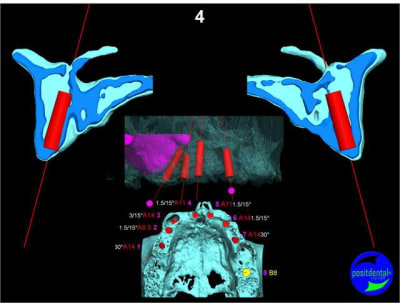

Extraction, pose d’implants Ankylos, pose des piliers Standard définitifs, mise en charge immédiate bi-maxillaire en une chirurgie.

Maxillaire supérieur – extraction 13, 26, 7 implants en MCI, 1 implant en MCR pose summeurs, densification par ostéotme, comblement osseux, bridge provisoire sans fausse gencive avec renfort métallique.

Maxillaire inferieur – extraction 35, 34, 44, 45, 6 implants MCI, comblement osseux, bridge provisoire sans fausse gencive avec renfort métallique.

en attendant la pano voici les coupes de la S.I.A.O.